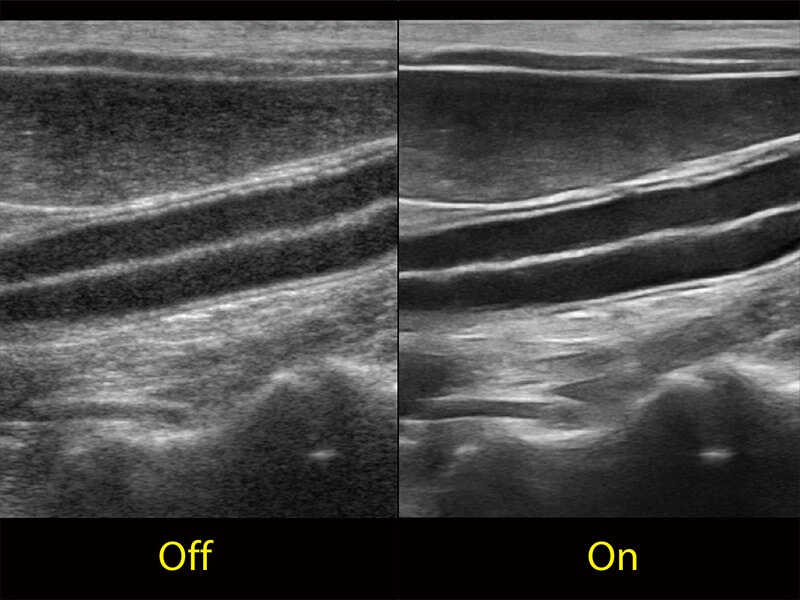

ProPet 60 作为一款高端台式动物超声设备,为动物医生的日常诊断提供了一系列贴合动物临床需求、解决临床实际问题的高级成像功能。凭借全系列高清探头,满足医生对腹部、心脏、生殖、浅表、肌骨等成像的所有需求,切实帮助您提升检查效率,提高诊断信心。